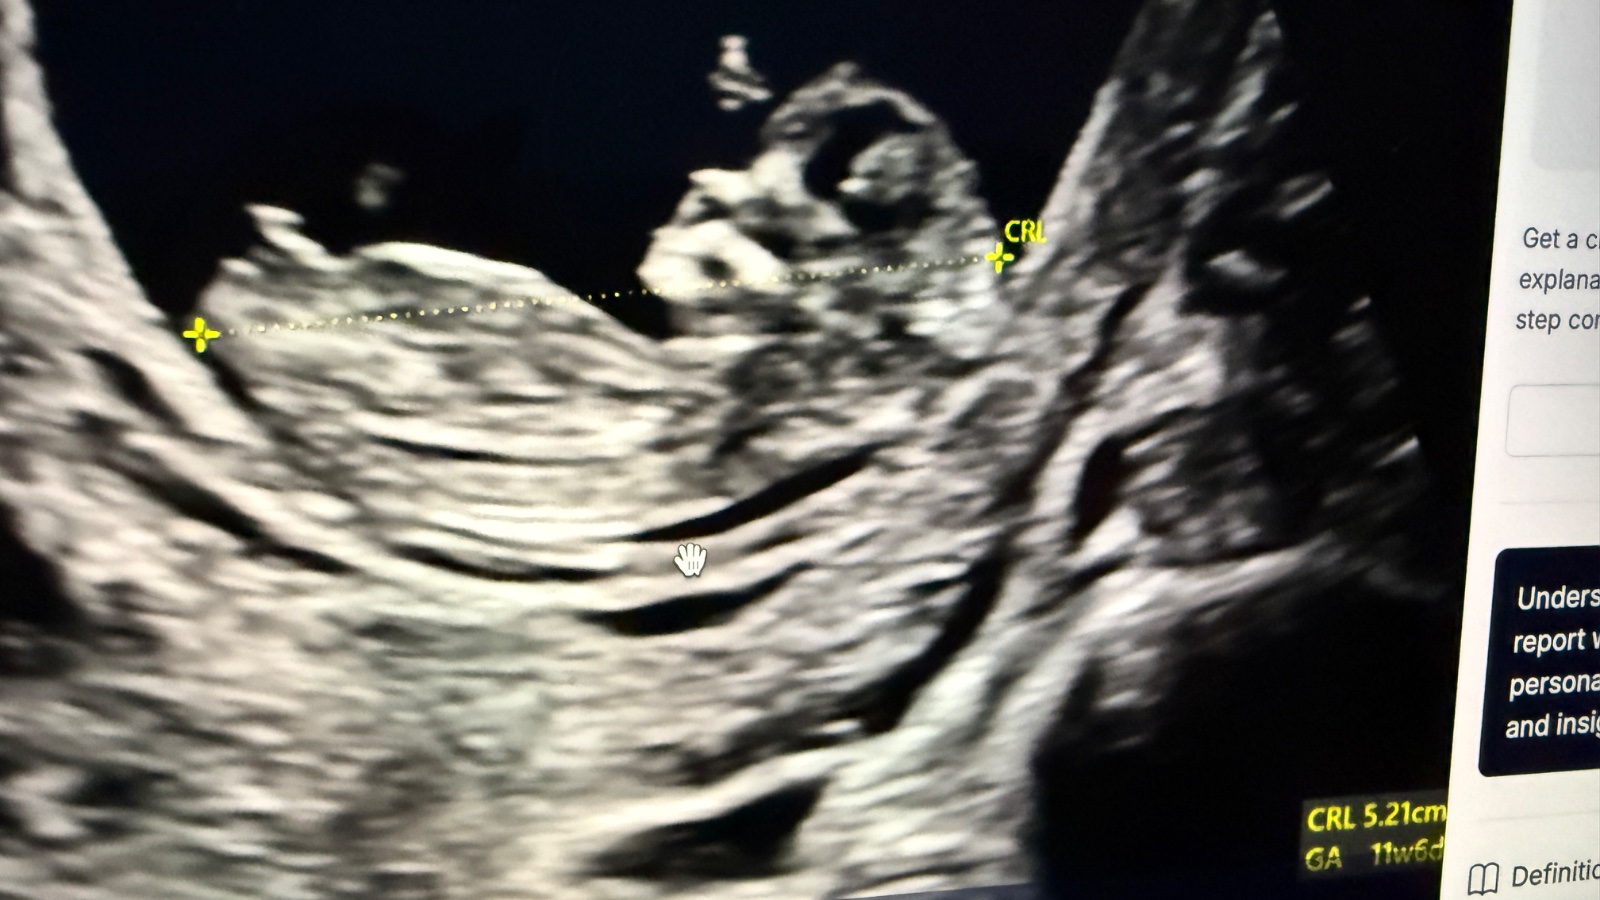

Prosím co by jste řekli u mě? 😁